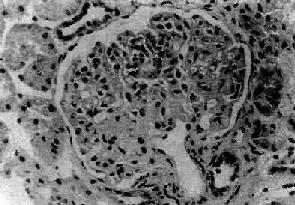

病变为局灶性,往往从肾皮质深部近髓质部分的少数肾小球开始。早期仅少数肾小球受累,其他肾小球无明显病变或病变轻微。病变的肾小球毛细血管丛的部分毛细血管萎陷,系膜增宽、硬化、玻璃样变(图12-21)。系膜内和毛细血管内常有脂滴和玻璃样物质沉积。有时可见吞噬脂类的泡沫细胞聚积。电镜下可见硬化部分毛细血管基底膜皱缩,厚薄不均匀。其间可见电子致密物和脂滴沉积。上皮细胞足突消失。免疫荧光检查可见病变肾小球内有免疫球蛋白和补体沉积,主要为IgM和C3。

图12-21 局灶性节段性肾小球硬化

肾小球毛细血管丛的一段硬化,玻璃样变